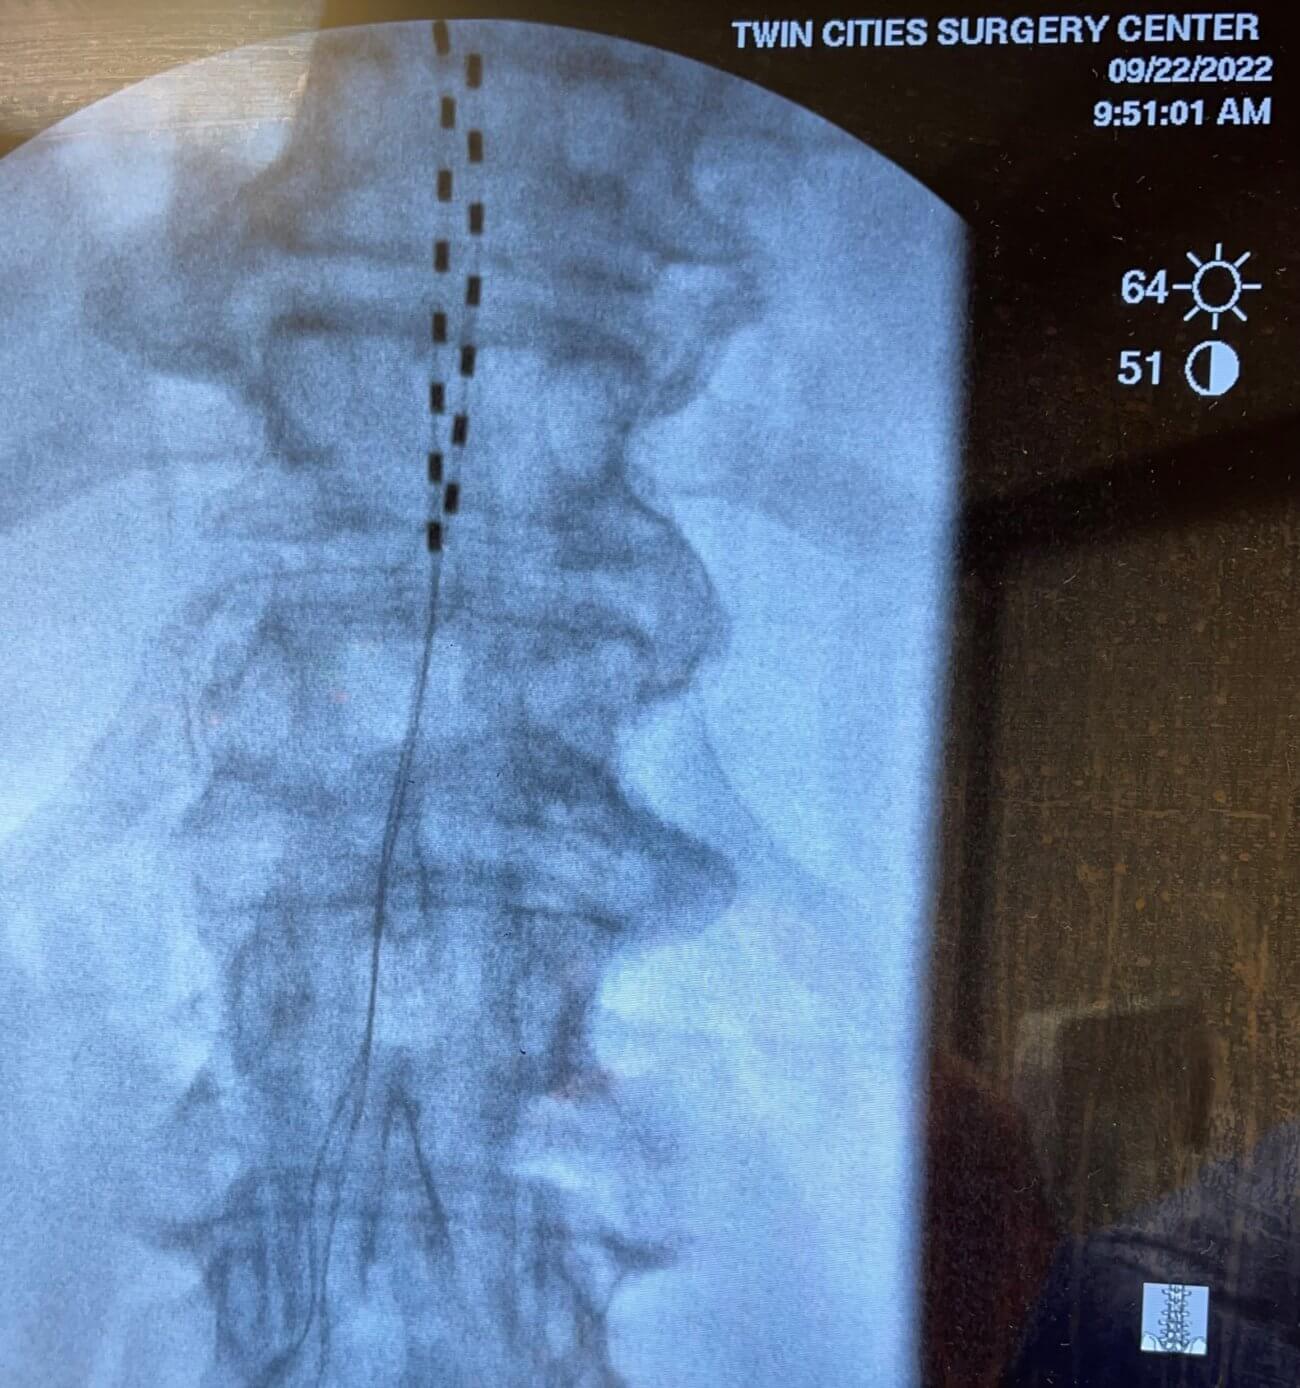

It is another significant FIRST for Twin Cities Pain Clinic! Our own Dr. Sherri Haas is the first female physician in the upper Midwest to implant the new Proclaim Plus™ spinal cord stimulation (SCS) system by Abbott. The procedure was completed on the morning of Thursday, September 22, 2022, at Twin Cities Surgery Center in Edina, Minnesota.

A pulse generator (essentially a small battery not much larger than a silver dollar) is implanted in the lower back. The generator emits electric pulses which are delivered by specialized wires (called leads) directly to the nerves associated with the patient’s pain.